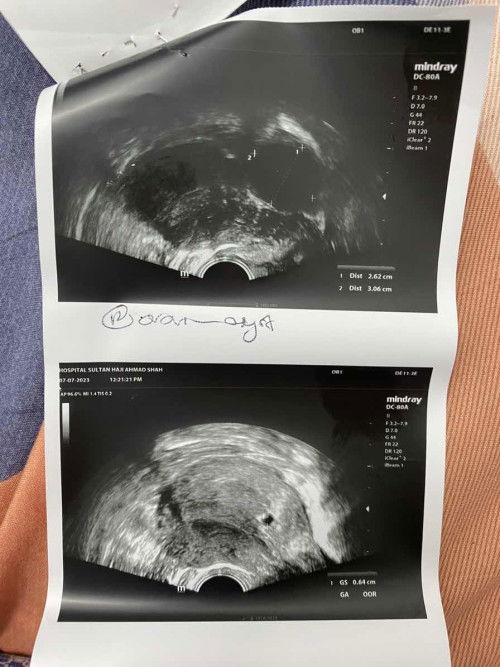

Sy nk tnya, ada tk yg pernh alami masalah mcm sy🥺 Semalam sy ada keluar spotting brown. Pastu sy ke klinik untuk cek masalah tu.. masa scan tiba2 ada cyst 2cm , dan yg kedua : kantung sy berada di bawah dekat dengan pintu keluar serviks mcm dlm gmbr tu..sepatutnya kantung tu berada di atas sikit.. ada tak yg pernah alami masalah mcm ni ? 🥺 #pleasehelp #firstbaby #seriusnanya #bantusharing #Spotting1sttrimester